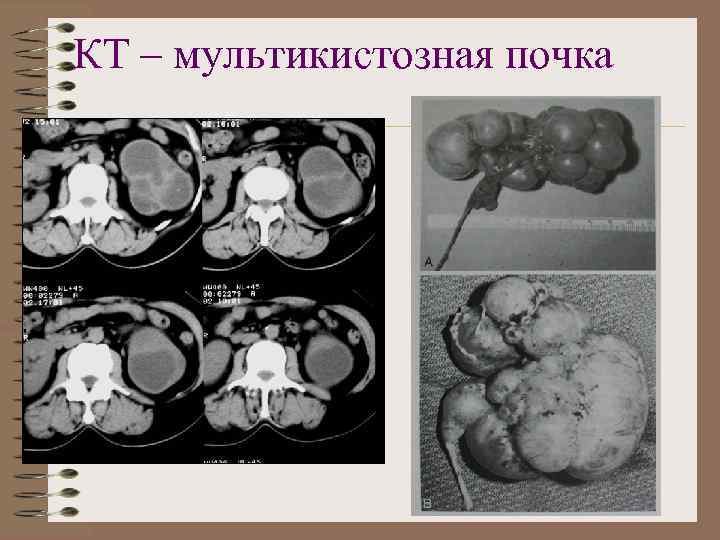

мультикистозная почка • Процесс всегда односторонний • В месте расположения почки - система кистозных полостей • Размеры либо превышают, либо меньше нормальной почки • Стенки кист толстые • Может быть обызвествление стенок • Лоханка, мочеточник не контрастируются

Мультикистозная почка Калициноз стенок кист

КТ – мультикистозная почка

Мультикистозная почка Кальциноз стенок